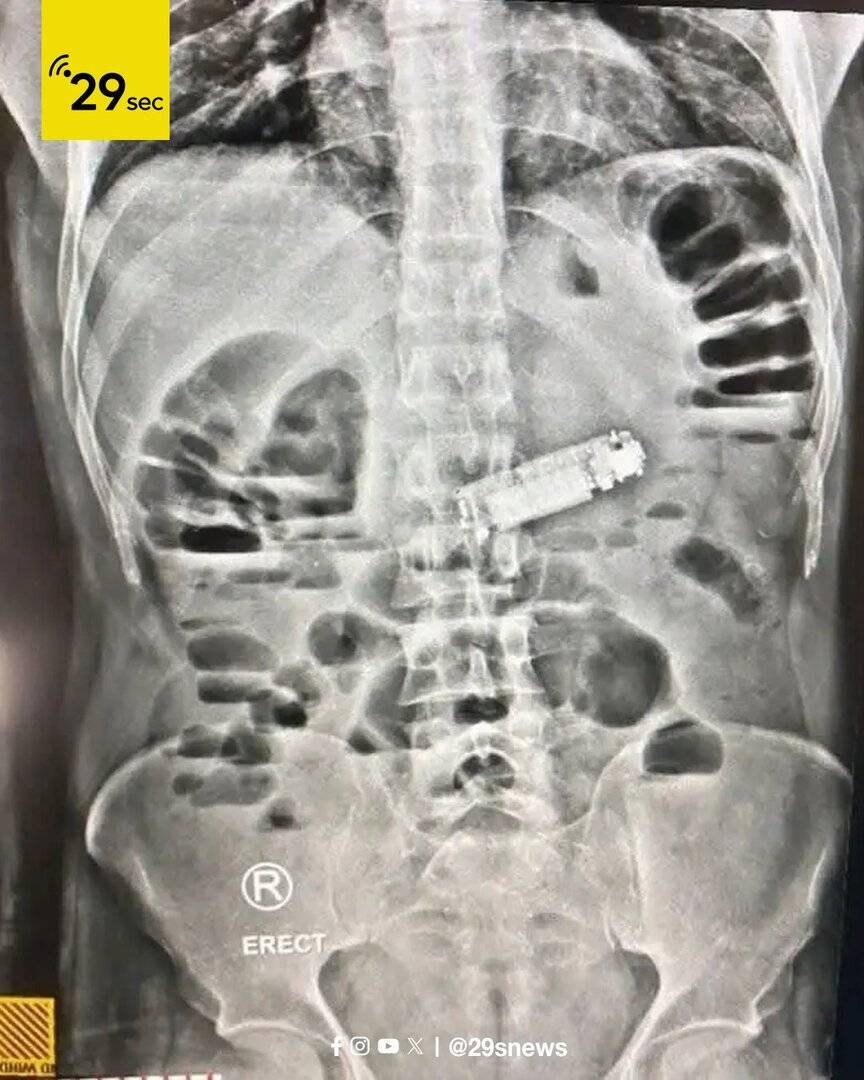

وبعد إجراء الفحوصات الطبية والأشعة اللازمة، تم الكشف عن وجود جسم غريب يسبب انسدادا في فتحة البواب في المعدة، وهو الهاتف المحمول.

عقب ذلك قام الفريق الطبي بإجراء العملية الجراحية الدقيقة، وتمكن من استخراج الهاتف بنجاح ودون مضاعفات، حيث استعاد المريض وعيه في قسم الإفاقة، وحالته الصحية مستقرة، ويخضع حاليا للملاحظة الطبية.